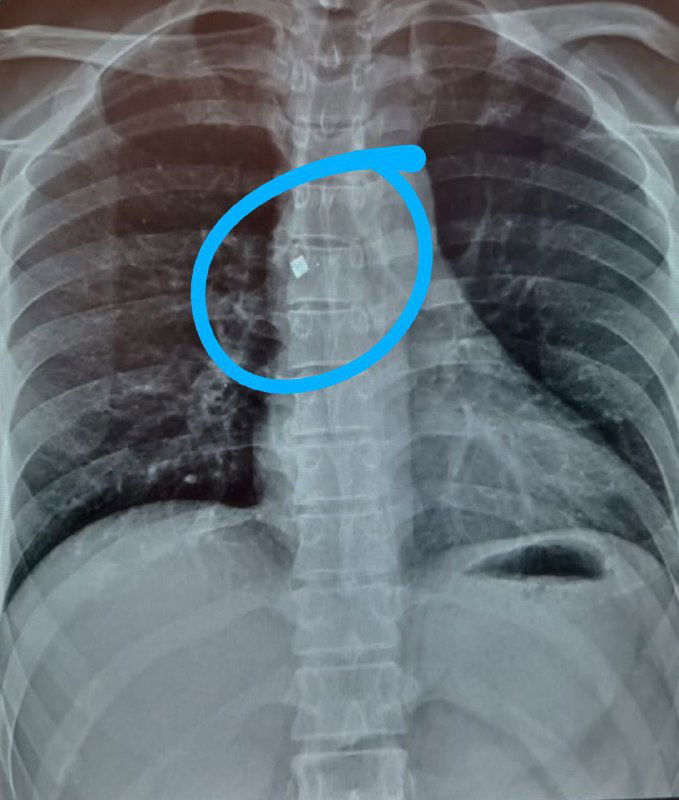

Эндоскопическое удаление металлического осколка из грудного отдела позвоночника